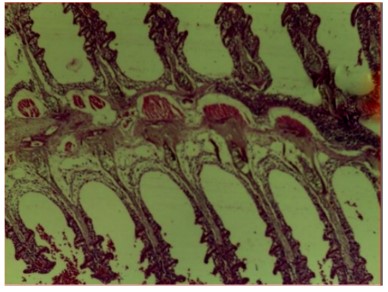

Histopathological examination of the liver and gill tissues of Clarias gariepinus juveniles revealed significant and concentration-dependent alterations following exposure to Bispyribac sodium herbicide, compared to the control groups, which displayed normal tissue architecture.

Similarly, the gill filaments (Fig. 8-13) of the control fish showed a normal structure of primary and secondary lamellae. Herbicide exposure caused progressive architectural disruption. Initial damage at 0.59 mg/L included haemorrhage (H) and enlargement of gill filaments (EGF). Higher concentrations (0.88-1.31 mg/L) introduced necrosis (N), distortion and shortening of filaments (DSF), and blood congestion (BC). At the highest concentrations (1.97-2.95 mg/L), the gills exhibited severe lamellar disorganization (LD) and, notably, hyperplasia of the lamellar epithelium (HLE) at 2.95 mg/L, indicating a severe defensive response to the toxicant.